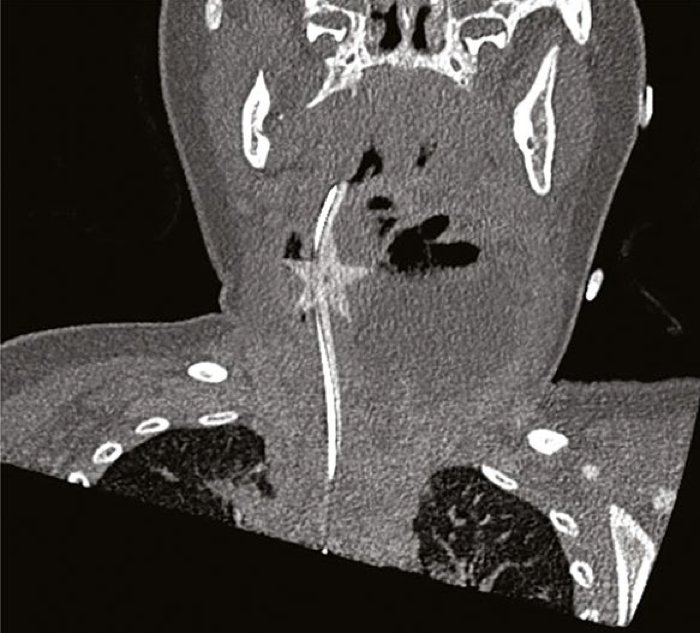

As a CT reconstruction clearly exhibits, a distinctly star-shaped object was additionally current within the little lady’s throat, lurking on the margins of the abcess: a five-pointed confetti star, embedded within the delicate tissue of her windpipe.

CT reconstruction displaying confetti star lodged in throat. (Heyworth & Shulman, MJA, 2019)